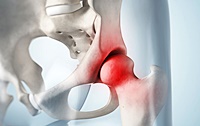

7. 고관절 골절

골밀도가 낮아지는 60대에 주로 발생하며, 고관절 골절 후에는 삶의 질이 크게 저하됩니다. 사망률도 높아져 심각한 질환입니다.